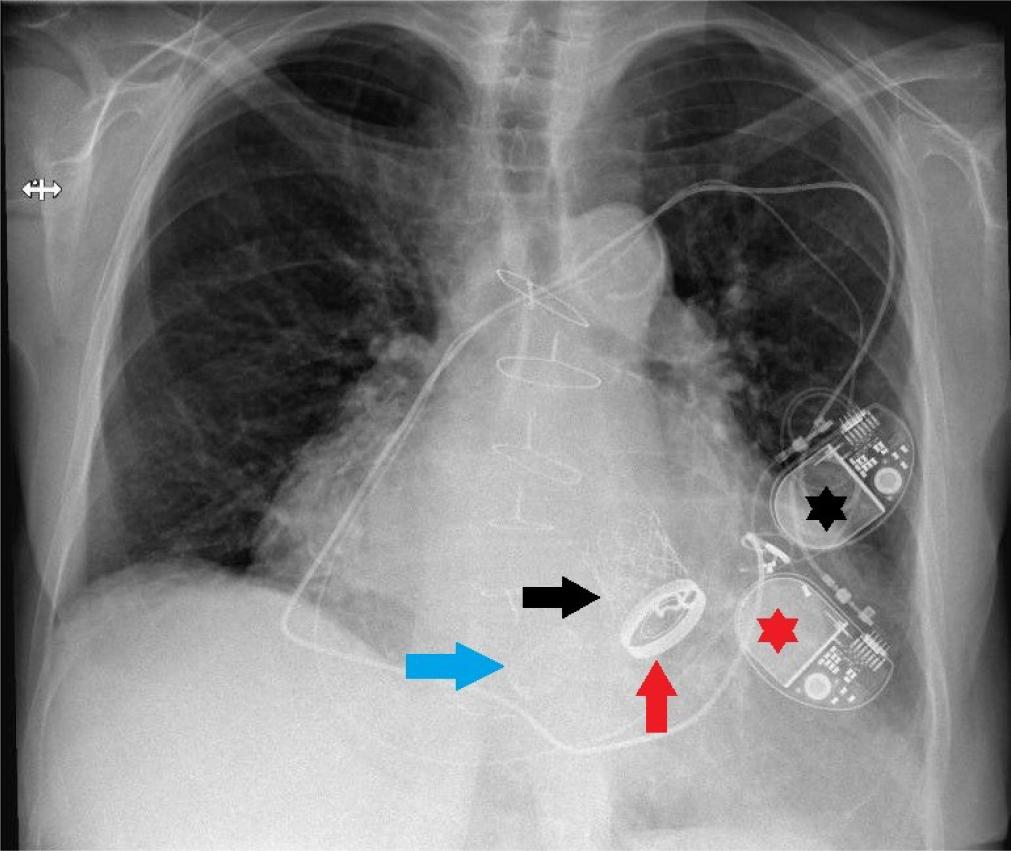

During the subsequent follow-up period, the patient experienced several hospitalizations due to recurrent presyncope, reporting significant variations in ventricular rate (50-140 bpm) at home – symptomatic primarily during episodes of slow heart rate. Holter ECG monitoring documented episodes of rapid AFib alternating with a ventricular-paced rhythm with intermittent failure to capture (pacing spikes not followed by QRS complexes), despite multiple attempts to reprogram the pacemaker. The issue was resolved upon realizing that the two pacing systems maintained in situ were interfering with each other due to their alternate interrogation at different times. Consequently, the most recently implanted device was reprogrammed to a non-functional mode and plans were made for its removal (Figure 5).

Chest X-Ray revealing the three different valve prosthese (blue arrow - tricuspid prosthesis, red arrow - mitral prosthesis, blac arrow - aortic prosthesis) and the two pacing systems (black asterisk first pacemaker, red asterisk - second pacemaker).